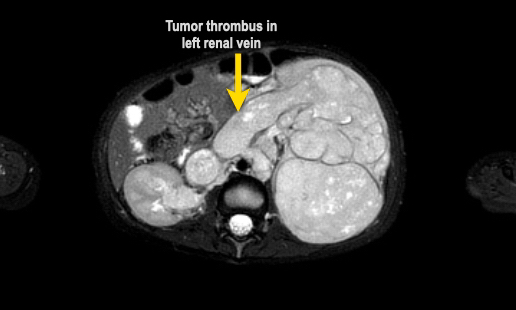

MRI có thể hiển thị rõ ràng huyết khối u trong tĩnh mạch thận và tĩnh mạch chủ dưới, cũng như tình trạng hạch bạch huyết to. Phương pháp này cho phép đo lường khối u một cách chính xác và có thể lặp lại trong các lần khám ban đầu và theo dõi.

Ví dụ 1

Một bé gái ba tuổi có khối u thận trái và huyết khối khối u lớn trong tĩnh mạch thận và tĩnh mạch chủ dưới. Có di căn gan (phát hiện không thường gặp) và di căn phổi.

Lưu ý huyết khối u trong tĩnh mạch thận trái kéo dài vào tĩnh mạch chủ dưới.